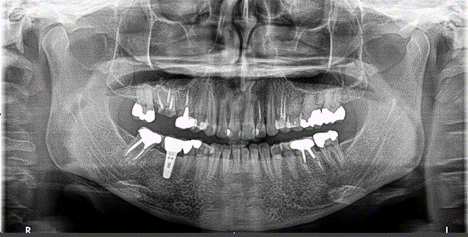

1. (Select ONE OR MORE correct answers)

Which of the following may complicate the extraction of tooth 3.5?

2. (Select ONE OR MORE correct answers)

Which of the following may complicate the extraction of tooth 4.7?

3. (Select ONE OR MORE correct answers)

4. Select ONE OR MORE correct answers)

Which of the following may complicate the extraction of tooth 1.7?

5. (Select ONE OR MORE correct answers)

Which of the following may complicate the extraction of tooth 3.8?

6. Select ONE OR MORE correct answers)

Which of the following may complicate the extraction of tooth 1.5?

7. Select ONE OR MORE correct answers)

Which of the following may complicate the extraction of tooth 2.7?

8. Select ONE OR MORE correct answers)

Which of the following may complicate the extraction of tooth 1.6?

9. Select ONE OR MORE correct answers)

Which of the following may complicate the extraction of tooth 1.3?

10. (Select ONE OR MORE correct answers.)

Which of the following may complicate the extraction of tooth 3.6?

11. (Select ONE OR MORE correct answers.)

Which of the following may complicate the extraction of tooth 4.5?

12. (Select ONE OR MORE correct answers.)

Tooth 4.8 is planned for extraction. Which radiographic findings suggest an increase in the degree of difficulty of the extraction?

13. (Select ONE OR MORE correct answers.)

Tooth 2.8 is planned for extraction. Which radiographic findings suggest an increase in the degree of difficulty of the extraction?

14. (Select ONE OR MORE correct answers.)

Which of the following may complicate the extraction of tooth 2.5?

15. (Select ONE OR MORE correct answers.)

Which of the following may complicate the extraction of tooth 2.2?

16. (Select ONE OR MORE correct answers.)

Tooth 1.8 is planned for surgical extraction. Which radiographic findings suggest an increase in the degree of difficulty of the extraction?

17. (Select ONE OR MORE correct answers)

Which of the following may complicate the extraction of tooth 7.4?

18. Select ONE OR MORE correct answers.)

Tooth 2.8 is planned for surgical extraction. Which radiographic findings suggest an increase in the degree of difficulty of the extraction?

19. (Select ONE OR MORE correct answers.)

Which of the following may complicate the extraction of tooth 3.7?

20. (Select ONE OR MORE correct answers.)

Which of the following may complicate the surgical extraction of tooth 1.6?

21. (Select ONE OR MORE correct answers.)

Which of the following may complicate the extraction of tooth 4.6?

22. (Select ONE OR MORE correct answers.)

Tooth 1.6 is planned for extraction. Which are the most likely postoperative complications?

23. Select ONE OR MORE correct answers)

Which of the following may complicate the extraction of tooth 1.4?

24. (Select ONE OR MORE correct answers.)

Tooth 3.8 is planned for extraction. Which are the most likely postoperative complications?

25. (Select ONE OR MORE correct answers.)